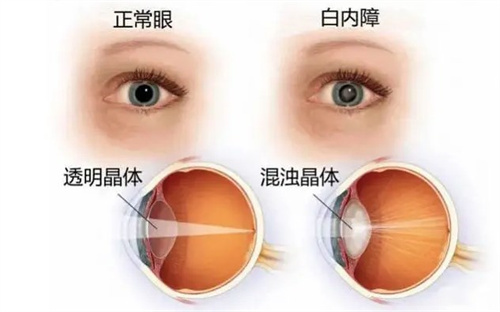

白内障超声乳化术:6800-12800元(不同晶体选择)

优势项目:白内障手术(使用进口晶体时比私立医院低30%)

特殊提醒:每周二下午的"银发关爱日"提供免费白内障筛查